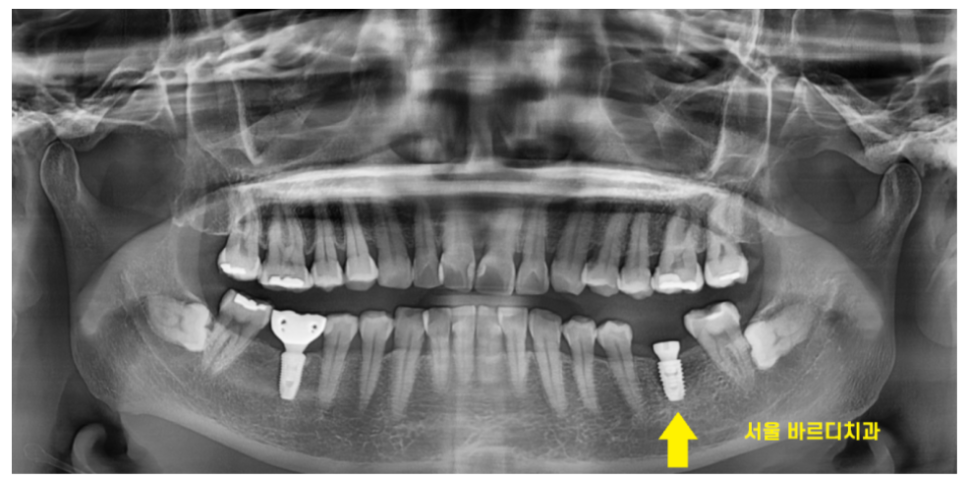

24.01.11

그래서 임플란트 크라운 크기

자연 치아에 비해 작습니다.

애초에 임플란트 크라운 크기

작게 만드니까요.

일반적으로 80-90%정도

작게 제작됩니다.

오래 사용하기 위하여!!

임플란트는 뼈에 고정되어있습니다.

자연치와 다른 특징중 하나가

충격을 흡수해주는 인대가 없다는 것이에요.